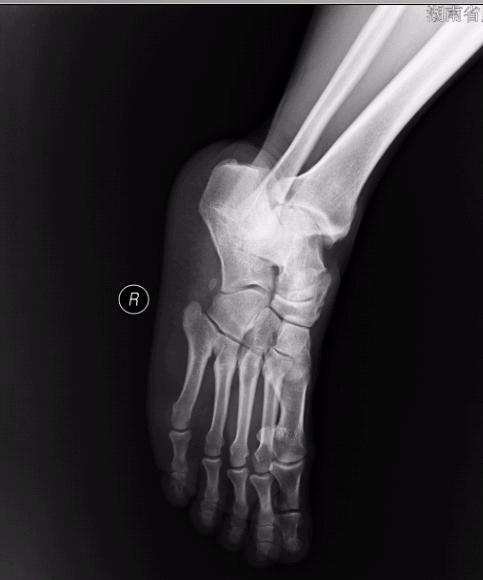

标题: X4772:10年手术 现在复发 足内侧硬肿块,无痛,活动不受 [打印本页]

标题: X4772:10年手术 现在复发 足内侧硬肿块,无痛,活动不受

舟附骨

可不要认为是舟骨骨折呦-----副舟骨---正常表现

副舟骨。

副舟骨,正常改变。如有症状为副舟骨综合症。

副舟骨综合症   是什么啊  老师们告诉我咯

我再次给病人写错了  写的是舟骨术后改变!!!!!!!!!!!!!!!!!!!!!!!!!!!!!还是带教老师让我写的!!!!!!!!!!!!!!!!!